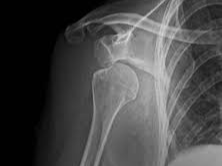

어깨 관절은 팔뼈(상완골), 견갑골, 쇄골 등 세 가지 주요 뼈와 이를 연결하는 근육, 힘줄, 인대 등으로 구성되어 있습니다. 특히 ‘회전근개(rotator cuff)’라고 불리는 네 개의 근육은 어깨의 회전과 안정성 유지에 중요한 역할을 합니다. 문제는 이 구조가 매우 유연하면서도 섬세하다는 점입니다. 작은 외상이나 반복적인 사용만으로도 손상이 일어나기 쉽습니다.